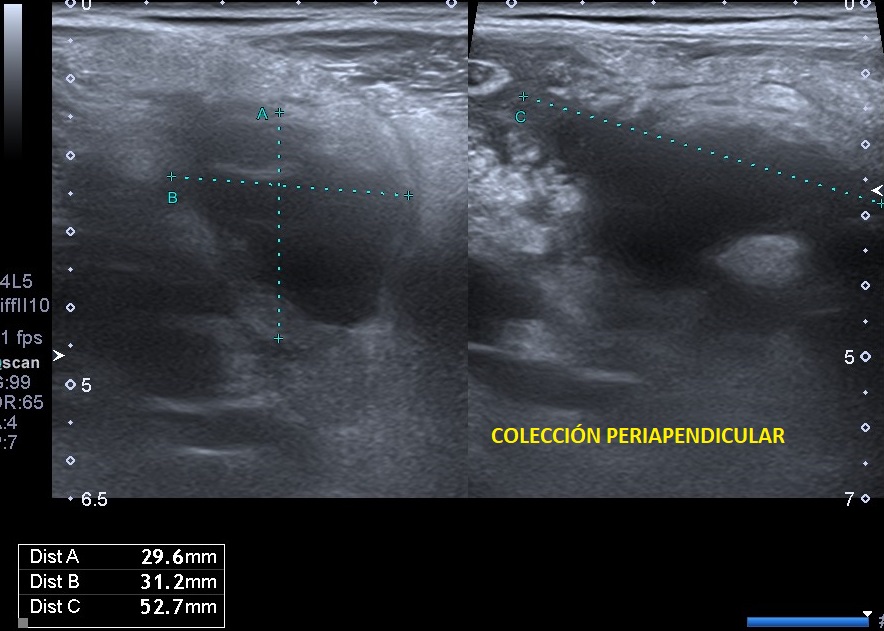

Se realiza una exploración abdominal ecográfica donde se observa hígado de ecogenicidad normal sin lesiones ocupantes de espacio. Vesícula biliar normal, vía biliar no dilatada. Ambos riñones de tamaño y aspecto normales. Páncreas, bazo y aorta normales. En fosa ilíaca derecha se observa apéndice cecal engrosado (imagen 1) con llamativa hiperecogenicidad de la grasa abdominal en relación con cambios inflamatorios (imagen 2). Colección abdominal en relación con cambios inflamatorios 3 x 3 x 5,3 cm (imagen 3).

La ecografía clínica se ha convertido en una herramienta útil para el diagnóstico temprano de apendicitis aguda. Gracias a su accesibilidad, permite realizar una evaluación rápida, ayudando a identificar signos como el engrosamiento del apéndice o la acumulación de líquido periapendicular.